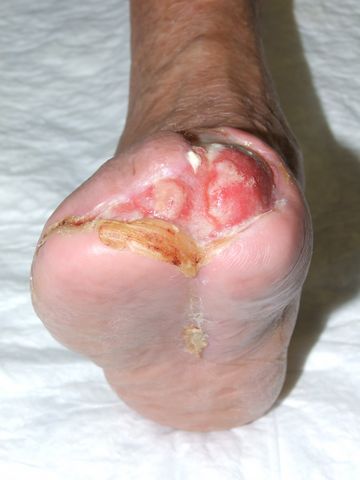

Mal perforante plantar en pie diabético

Mal perforante plantar. Pie diabético.